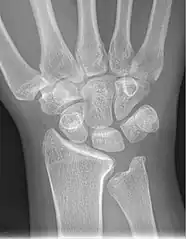

Negative ulnar variance. -

Left hand x-ray with Kienbock's Disease showing 4 mm negative ulnar variance and Kienbock's Disease Stage IIIB -

Left hand x-ray with Kienbock's Disease -